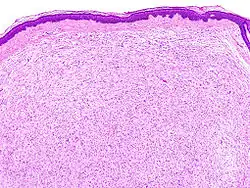

Neurofibrom je nezhoubný nádor vyrůstající z nervového obalu, podobný neurinomu. Často jím trpí pacienti s neurofibromatózou prvního typu (NF1). Projevuje se širokým rozsahem postižení v oblasti bolesti a kognitivních funkcí. Nemoc vzniká z neomyelinizujích Schwanových buněk, které vykazují neaktivní NF1 gen, který kóduje neurofibromin. Neurofibrom se dělí na dva základní podtypy: dermalní a plexiformní.

Většinou tvoří dobře ohraničenou neopouzdřenou lézi v submukóze, histologicky sestávající z protáhlých a zvlněných vřetenitých buněk s blandními zašpičatělými jádry. Imunohistochemicky lze prokázat polymorfní složení nádoru ze Schwannových buněk, fibroblastů, axonů a případně i perineurálních buněk.[1] Oba typy se léčí operativním odstraněním.